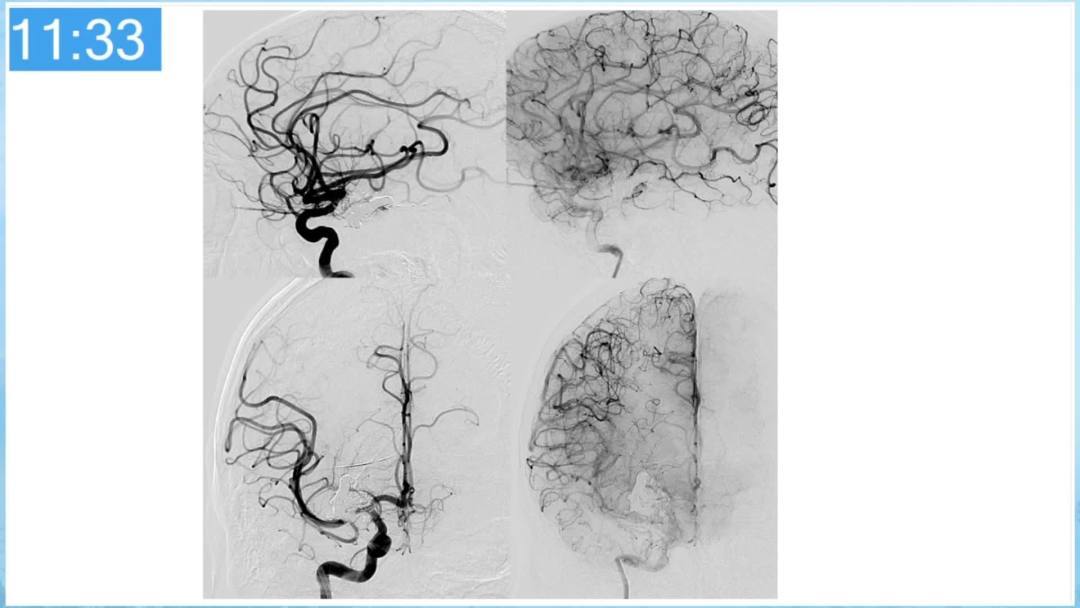

合理的复合平台下的综合治疗,针对每一个病变对应不同方法安全性分析,不预设、不排斥,每种技术发挥到最佳,互相保障。

本期为大家特别分享:空军军医大学唐都医院邓剑平教授的精彩会议内容《颅内动静脉畸形的复合手术治疗》,欢迎大家阅读和分享!